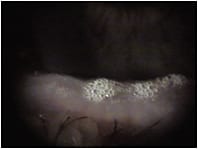

» Figure 2. Highly saturated, thick meibum on lid margins.

However, most of the patients I see have significant MGD. As MGD progresses, the glands become increasingly obstructed and lipids stagnate — becoming thick, saturated and stagnant. Glands may have obvious plugs or dilated orifices, and expressing them produces a cheesy or toothpaste-like substance, if anything. This secretion isn’t simply non-functional or sparse — the highly saturated oils also can contaminate the normal lipids within the tear film.